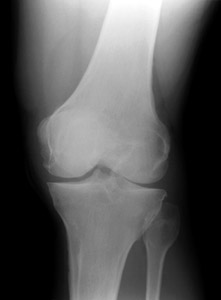

Patellar Fracture

Oblique view |

AP view | |

Fractures of the patella can be confused with bipartite or multipartite patella. The radiographs below

show bipartite patella. Compare the images below with those shown above. Notice that the fractured

patella has pieces that fit together like a jigsaw puzzle. The bipartite or multipartite patella has

pieces with more rounded margins that do not fit together. | ||